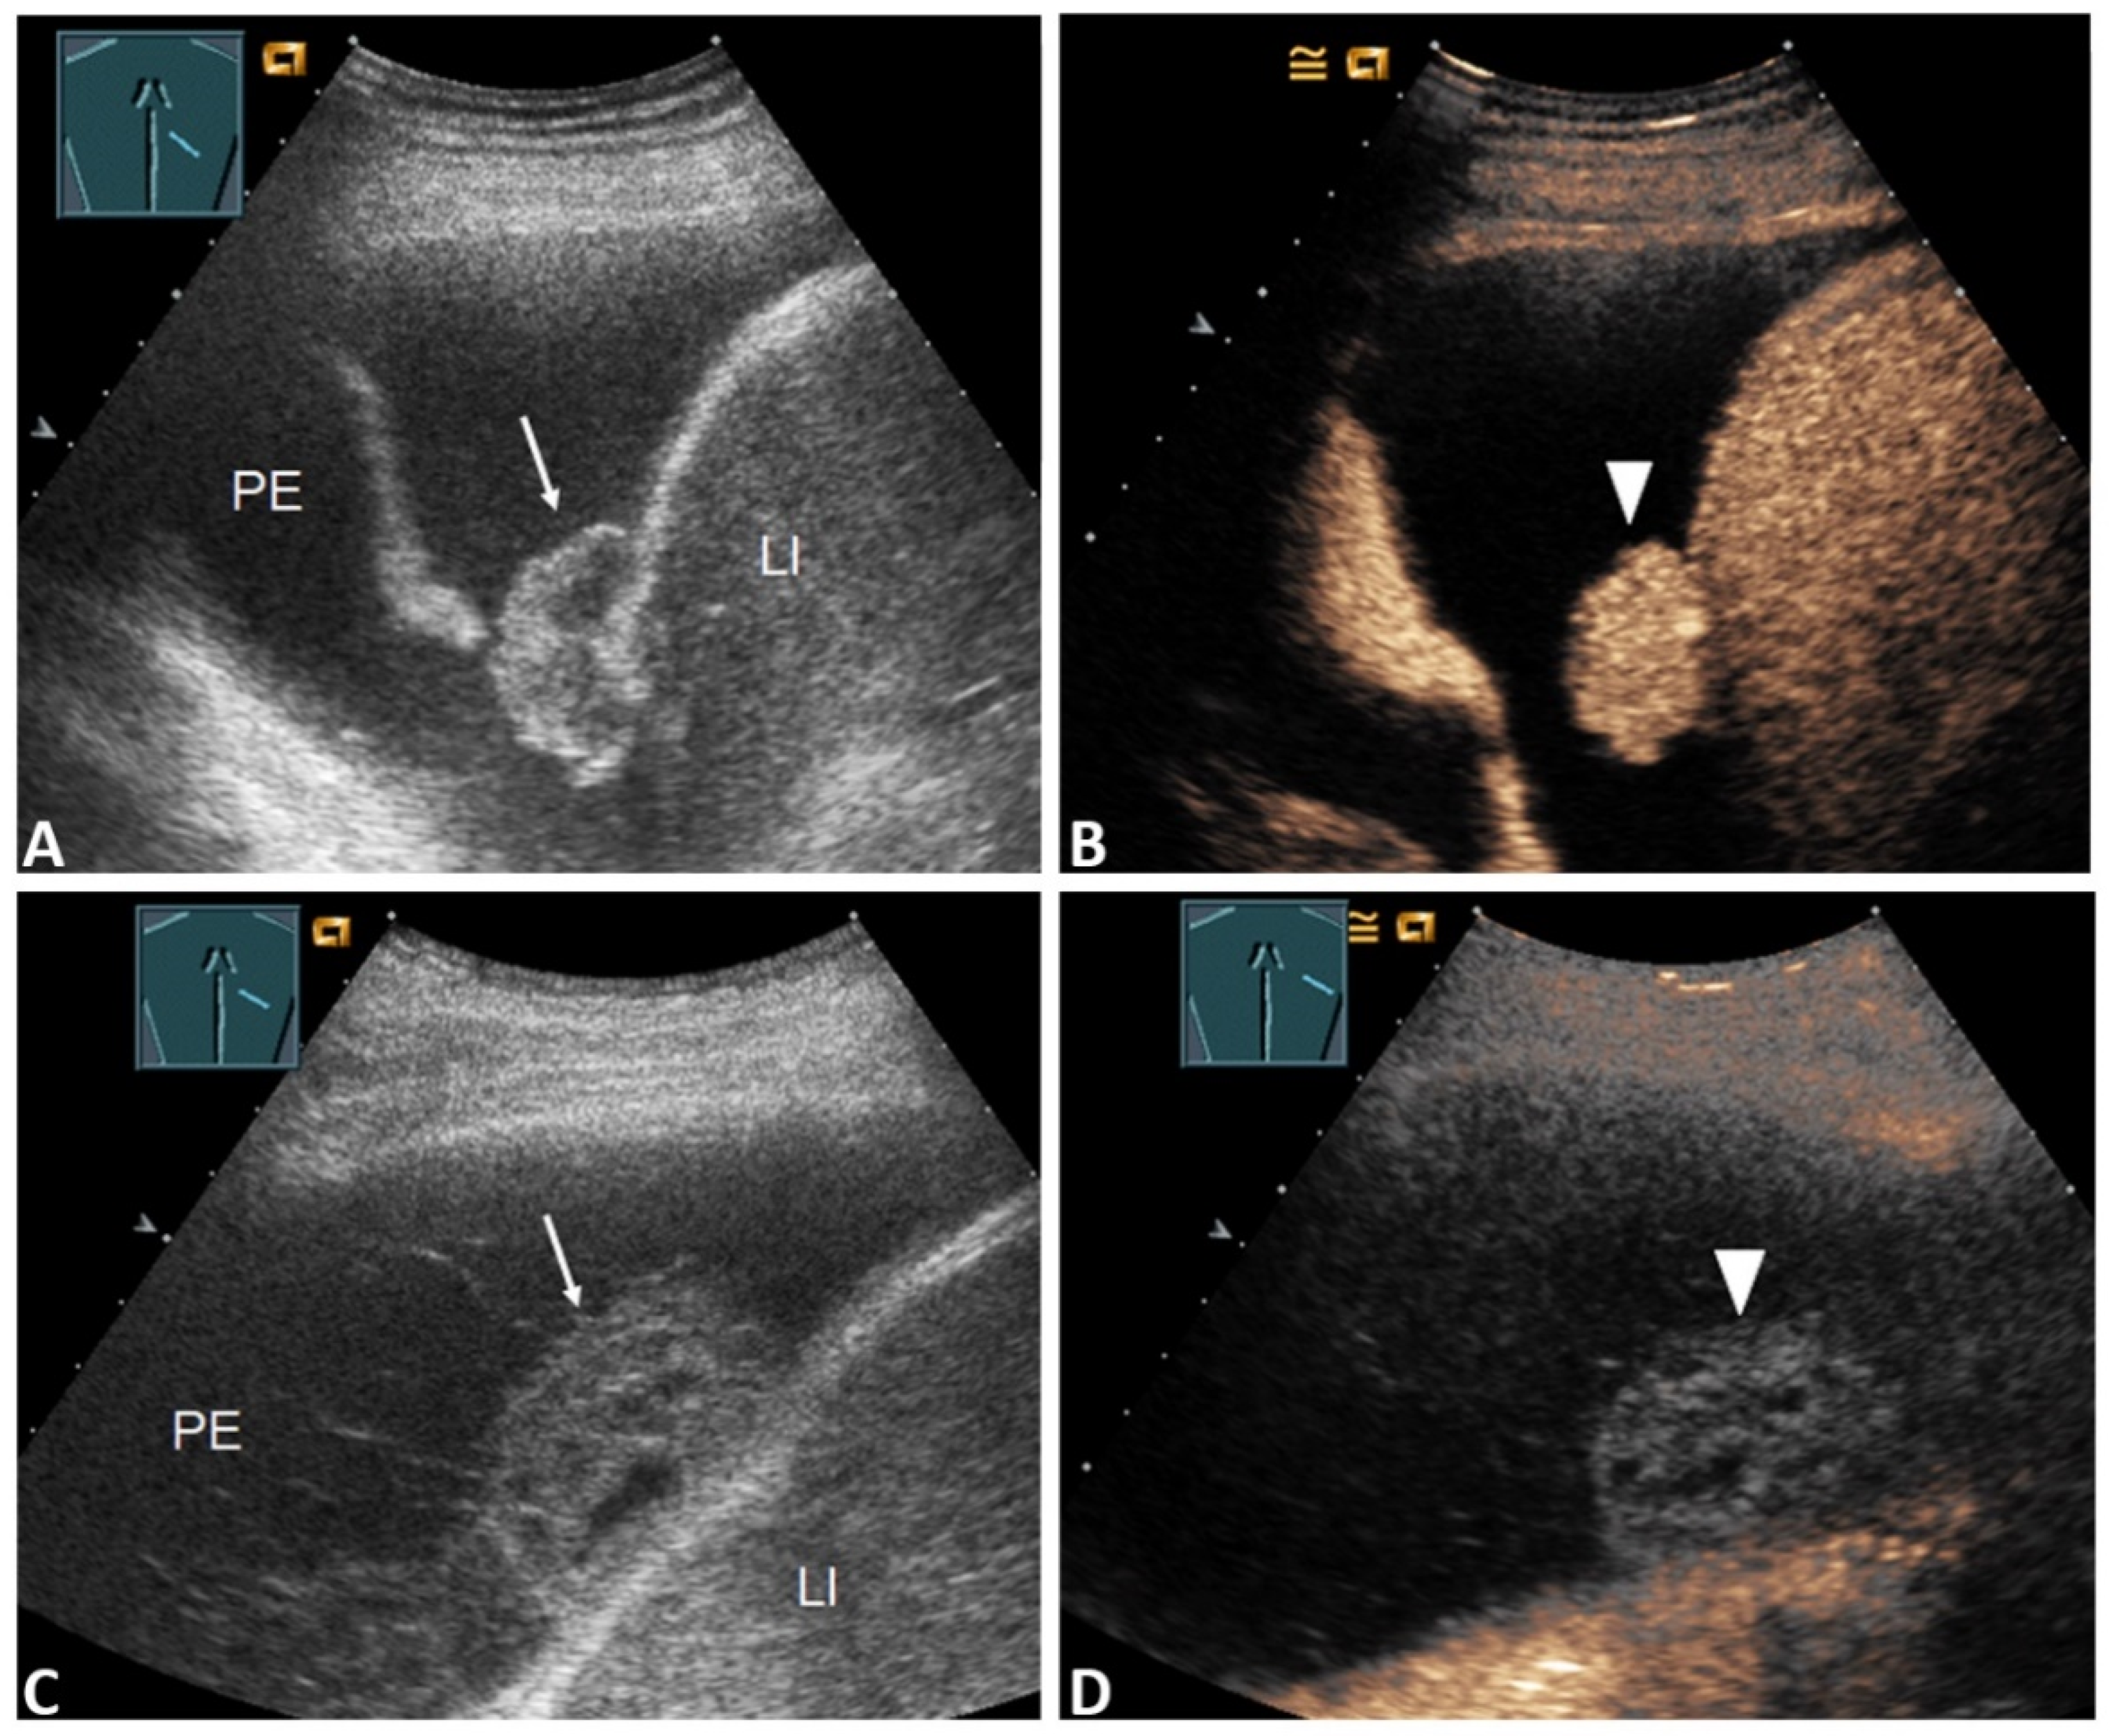

| Pleural thickening with marked enhancement (Figure 2B and Figure 3D) | 27 (32.5%) | 20 (47.6%) | 7 (17.1%) | 0.005 * |

| Pleural thickening with absent or reduced enhancement or no pleural thickening (Figure 3B) | 56 (67.5%) | 22 (52.4%) | 34 (82.9%) | |

| Inhomogeneous enhancement of lung consolidation (Figure 5B–D) | 25 (30.1%) | 19 (45.2%) | 6 (14.6%) | 0.004 * |